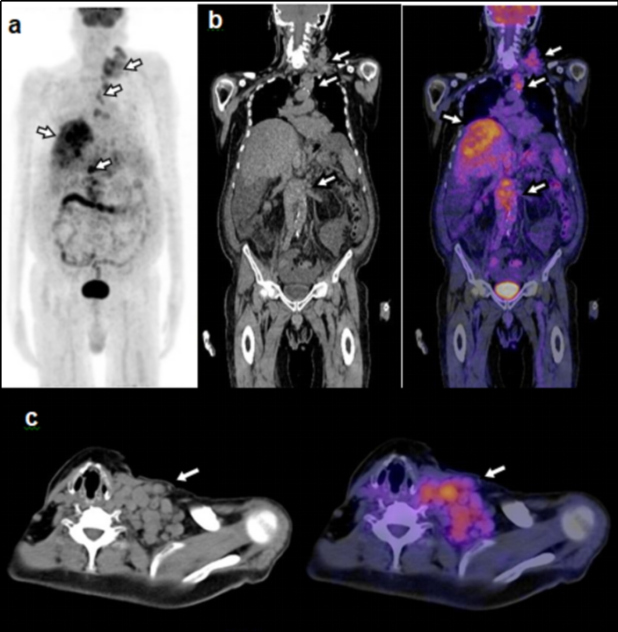

El ID calculado considerando los pacientes con etiología maligna confirmada mediante biopsia o seguimiento, arrojó un valor de 47%. La proporción de FP tomando en cuenta aquellos pacientes con al menos un hallazgo positivo en el PET-CT con otra etiología confirmada que no fuera maligna y aquellos en los cuales no fue posible determinar el tipo de etiología mediante biopsia o seguimiento, fue de 27%. De los pacientes en los que se encontró una etiología maligna, 49 casos fueron confirmados mediante biopsia y 1 mediante seguimiento. De los pacientes con biopsia, el diagnóstico de anatomía patológica más frecuente fue el adenocarcinoma pobremente diferenciado (tabla 1). En cuanto a localización, el sitio primario más común fue el pulmón, seguido del páncreas (tabla 2). Las figuras 1-4 ilustran algunos casos representativos de nuestra serie.